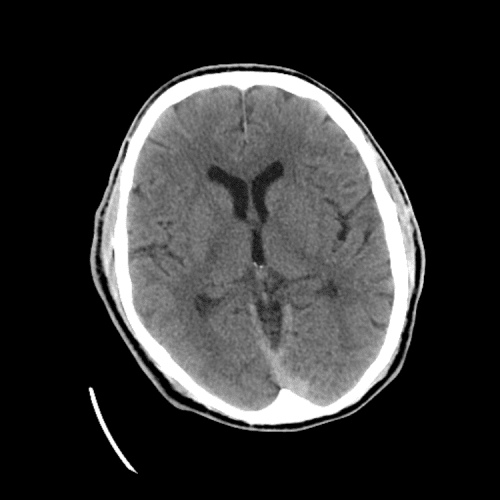

ACA and MCA territory infarct

PCA infarct